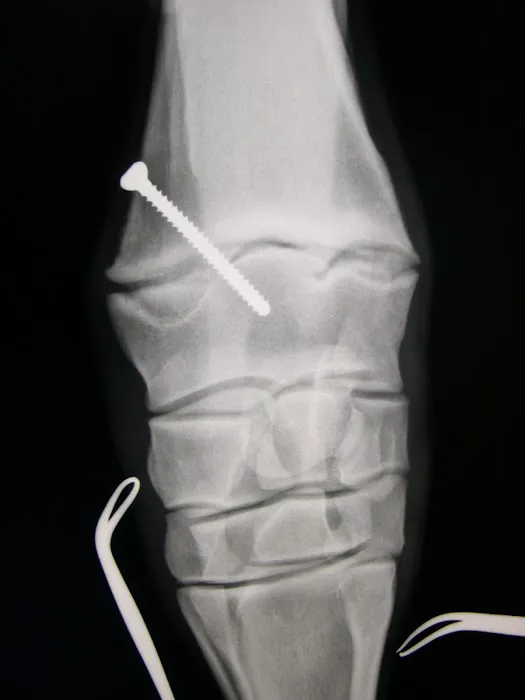

- Surgical Services: General and specialized surgical procedures, including Minimally Invasive Surgery (Arthroscopy, Laparoscopy, Thoracoscopy), Laser Surgery, and a dedicated surgical suite and padded recovery rooms.

- Board-Certified Specialists: The team includes board-certified veterinarians (Diplomates of the American College of Veterinary Surgeons - ACVS, for example), providing the highest level of specialized expertise in surgery, lameness, and internal medicine.

- Comprehensive Surgical Services: They offer a full surgical suite and expertise in advanced surgical techniques, including Laser Surgery and minimally invasive procedures, which typically result in faster recovery times for the patient.

Choosing Equine Services, PSC is a choice for peace of mind, knowing your horse is receiving some of the best care available in Kentucky. Horse owners value the combination of world-class expertise and local convenience that this facility provides. As a full-service equine hospital, they eliminate the need for owners to seek advanced diagnostics or surgical treatment elsewhere, saving valuable time during emergencies or complex cases. The ability to perform advanced procedures, from sophisticated Lameness Evaluation using Digital Radiography and MRI to complex Orthopedic Procedures, all under one roof, is a significant advantage.